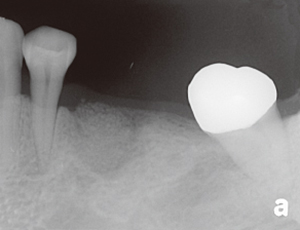

未經牙周病治療的牙齒,幾年後....

本院實例:

牙周病會造成牙齦發炎流血,齒槽骨牙周韌帶的破壞,最終導致牙齒的脫落。成人的牙齒脫落原因中有75%是因為牙周病造成的。